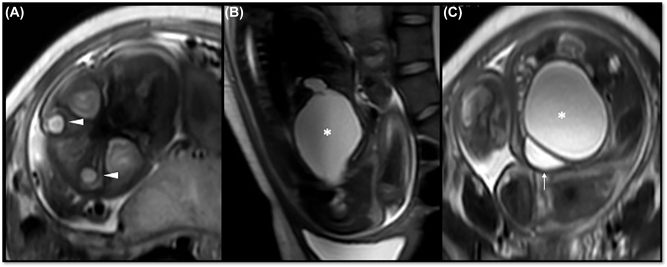

Case presentation: A 19-year-old primigravida presenting at 35 weeks of gestation, with prenatal finding of hydrometrocolpos associated with hypotelorism and microphthalmia. Pre-term cesarean delivery was performed due to breech labor and perinatal death. The autopsy confirmed hydrometrocolpos secondary to vaginal atresia and imperforate hymen, associated with cryptophthalmos, syndactyly, nasal and pinna malformations, confirming the diagnosis of Fraser syndrome.

Conclusions: Fraser syndrome is usually a postnatal diagnosis. The association with genital abnormalities explains the finding of hydrometrocolpos, which could be considered a diagnostic criterion for this syndrome.